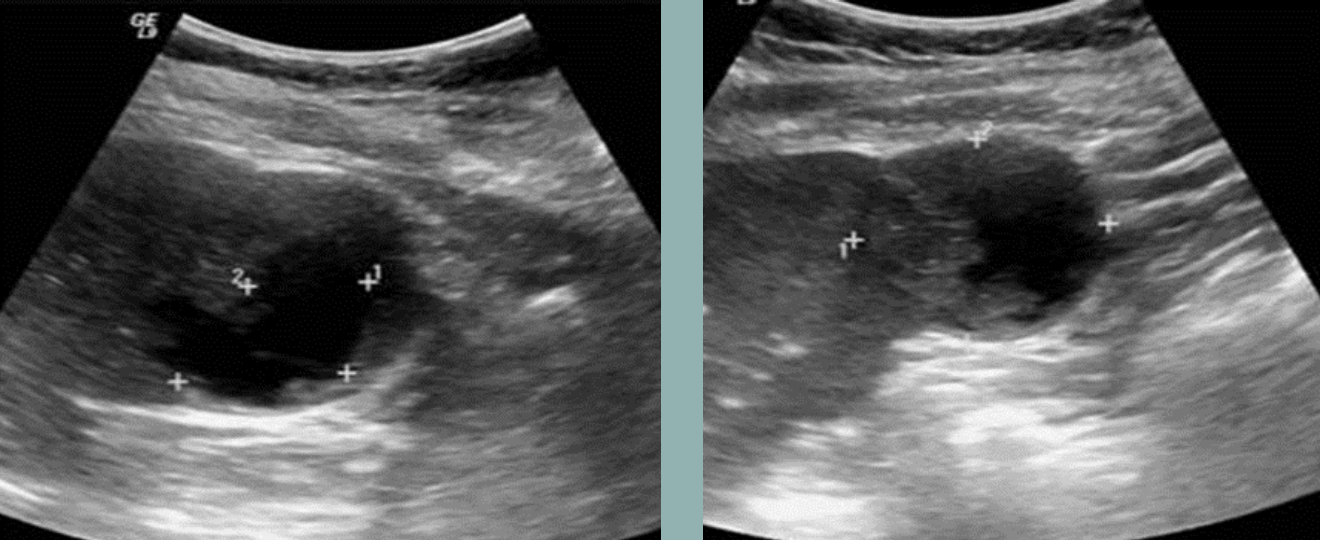

Pancreatic Pseudocyst → peripancreatic fluid collection from trauma or pancreatitis (4-6 week onset after pancreatitis)

2D US: not always spherical, usually located in lesser sac (anterior to pancreas and posterior to stomach)

color doppler: avascular

DDX: true cyst